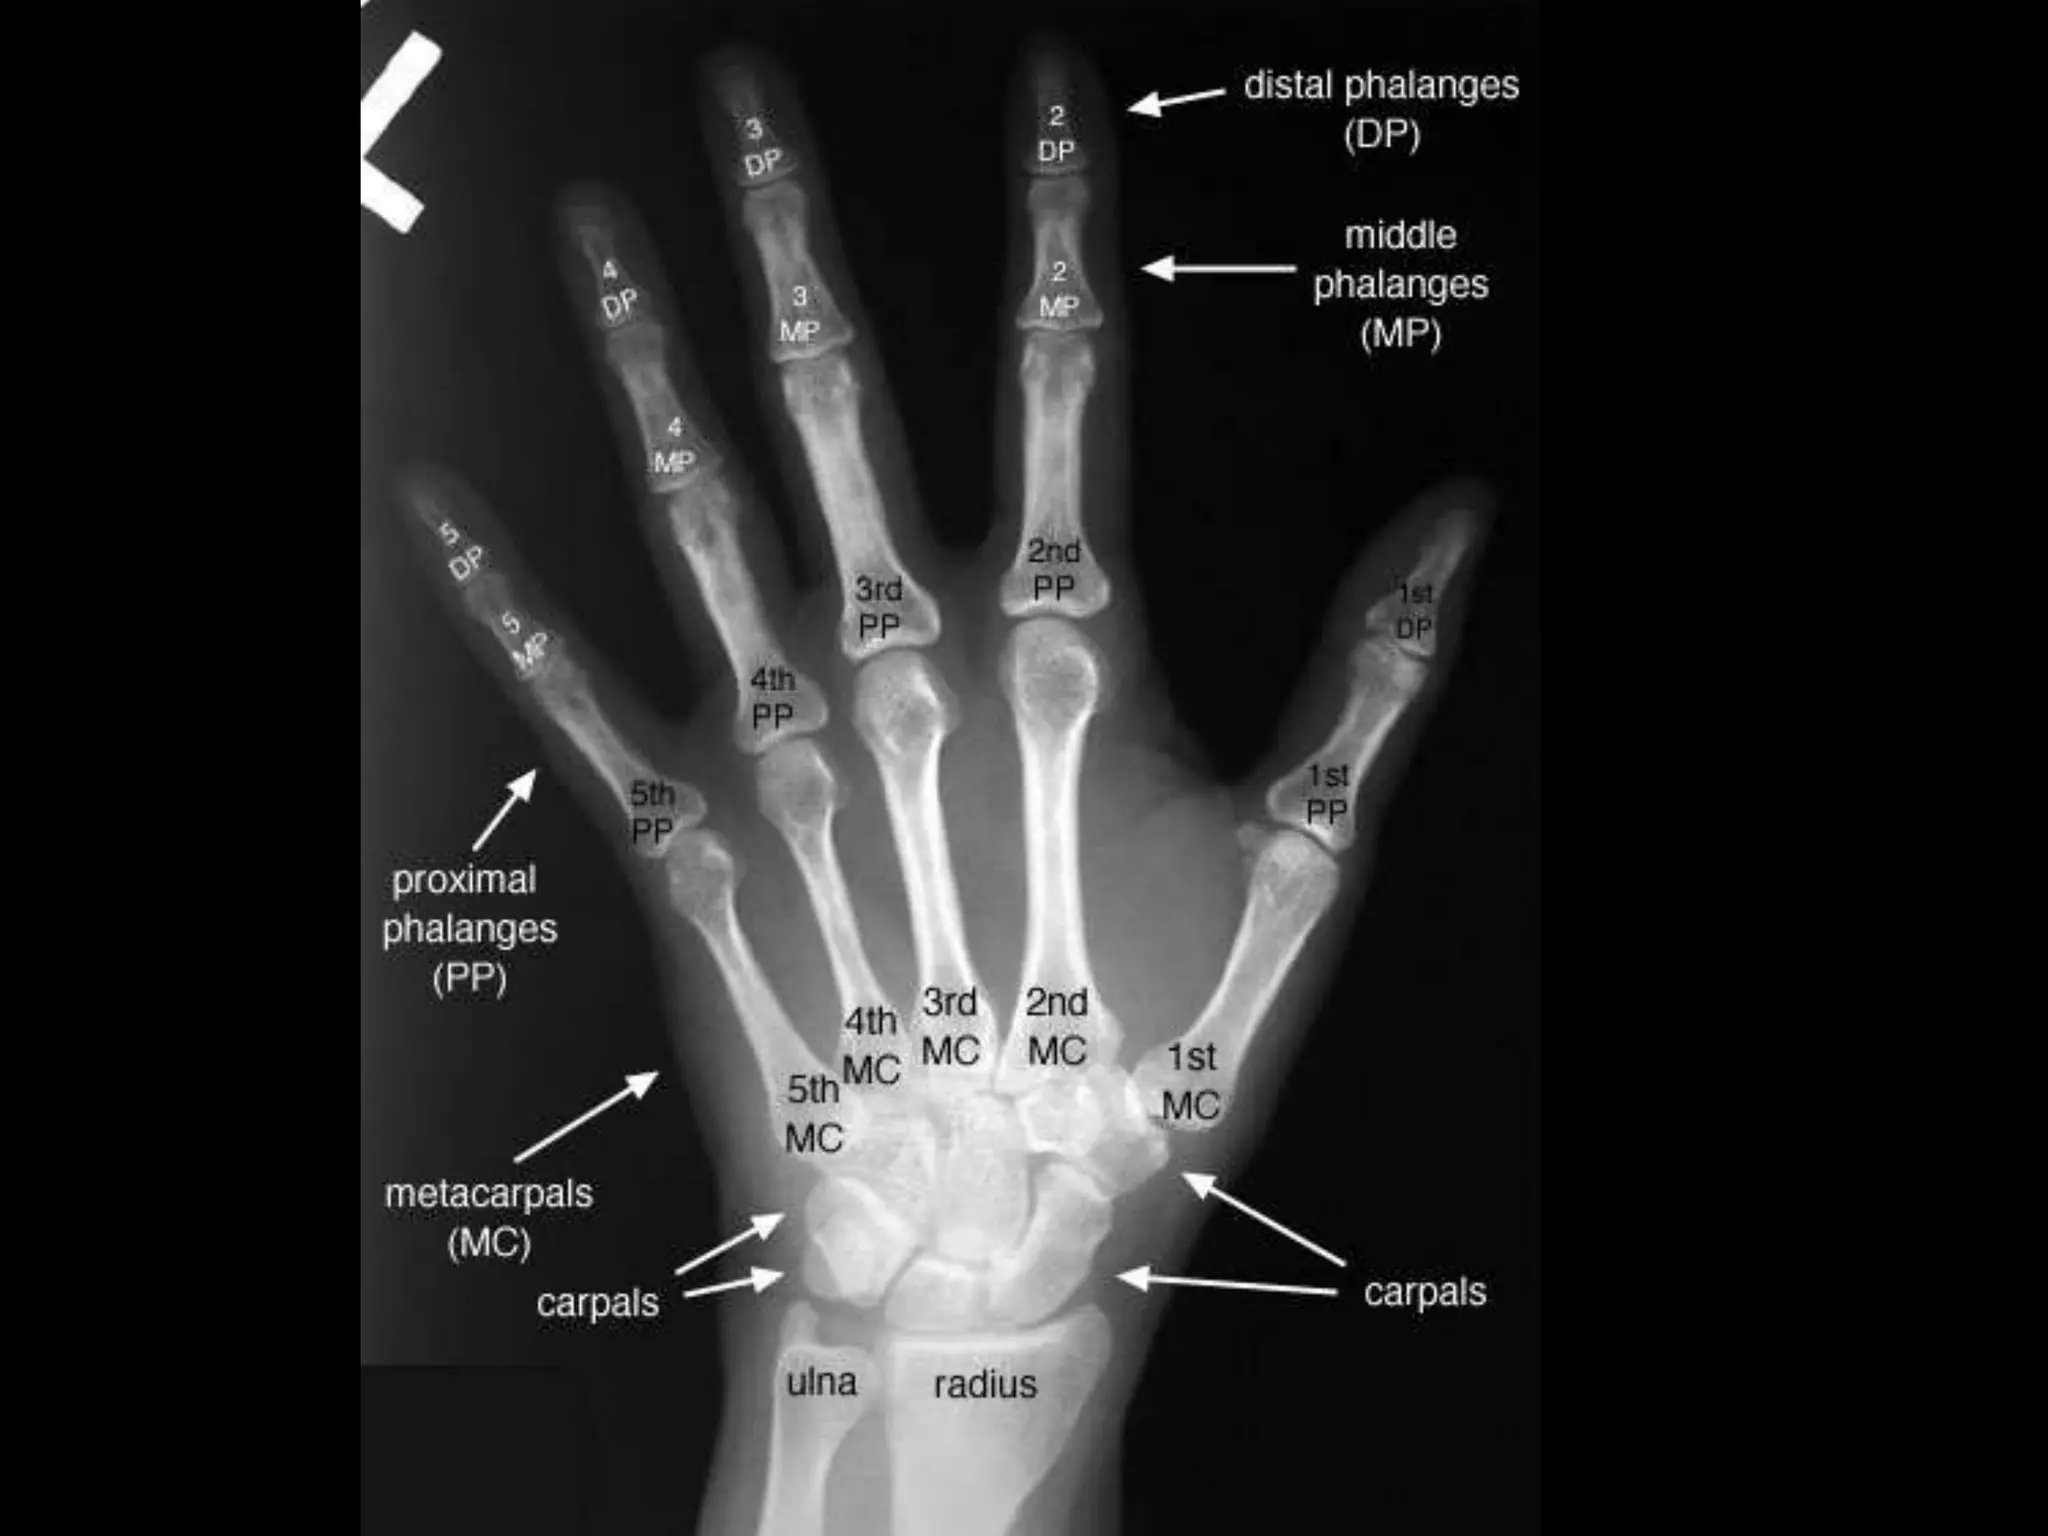

- Pelvic Bones

- Hand Wrist X-ray